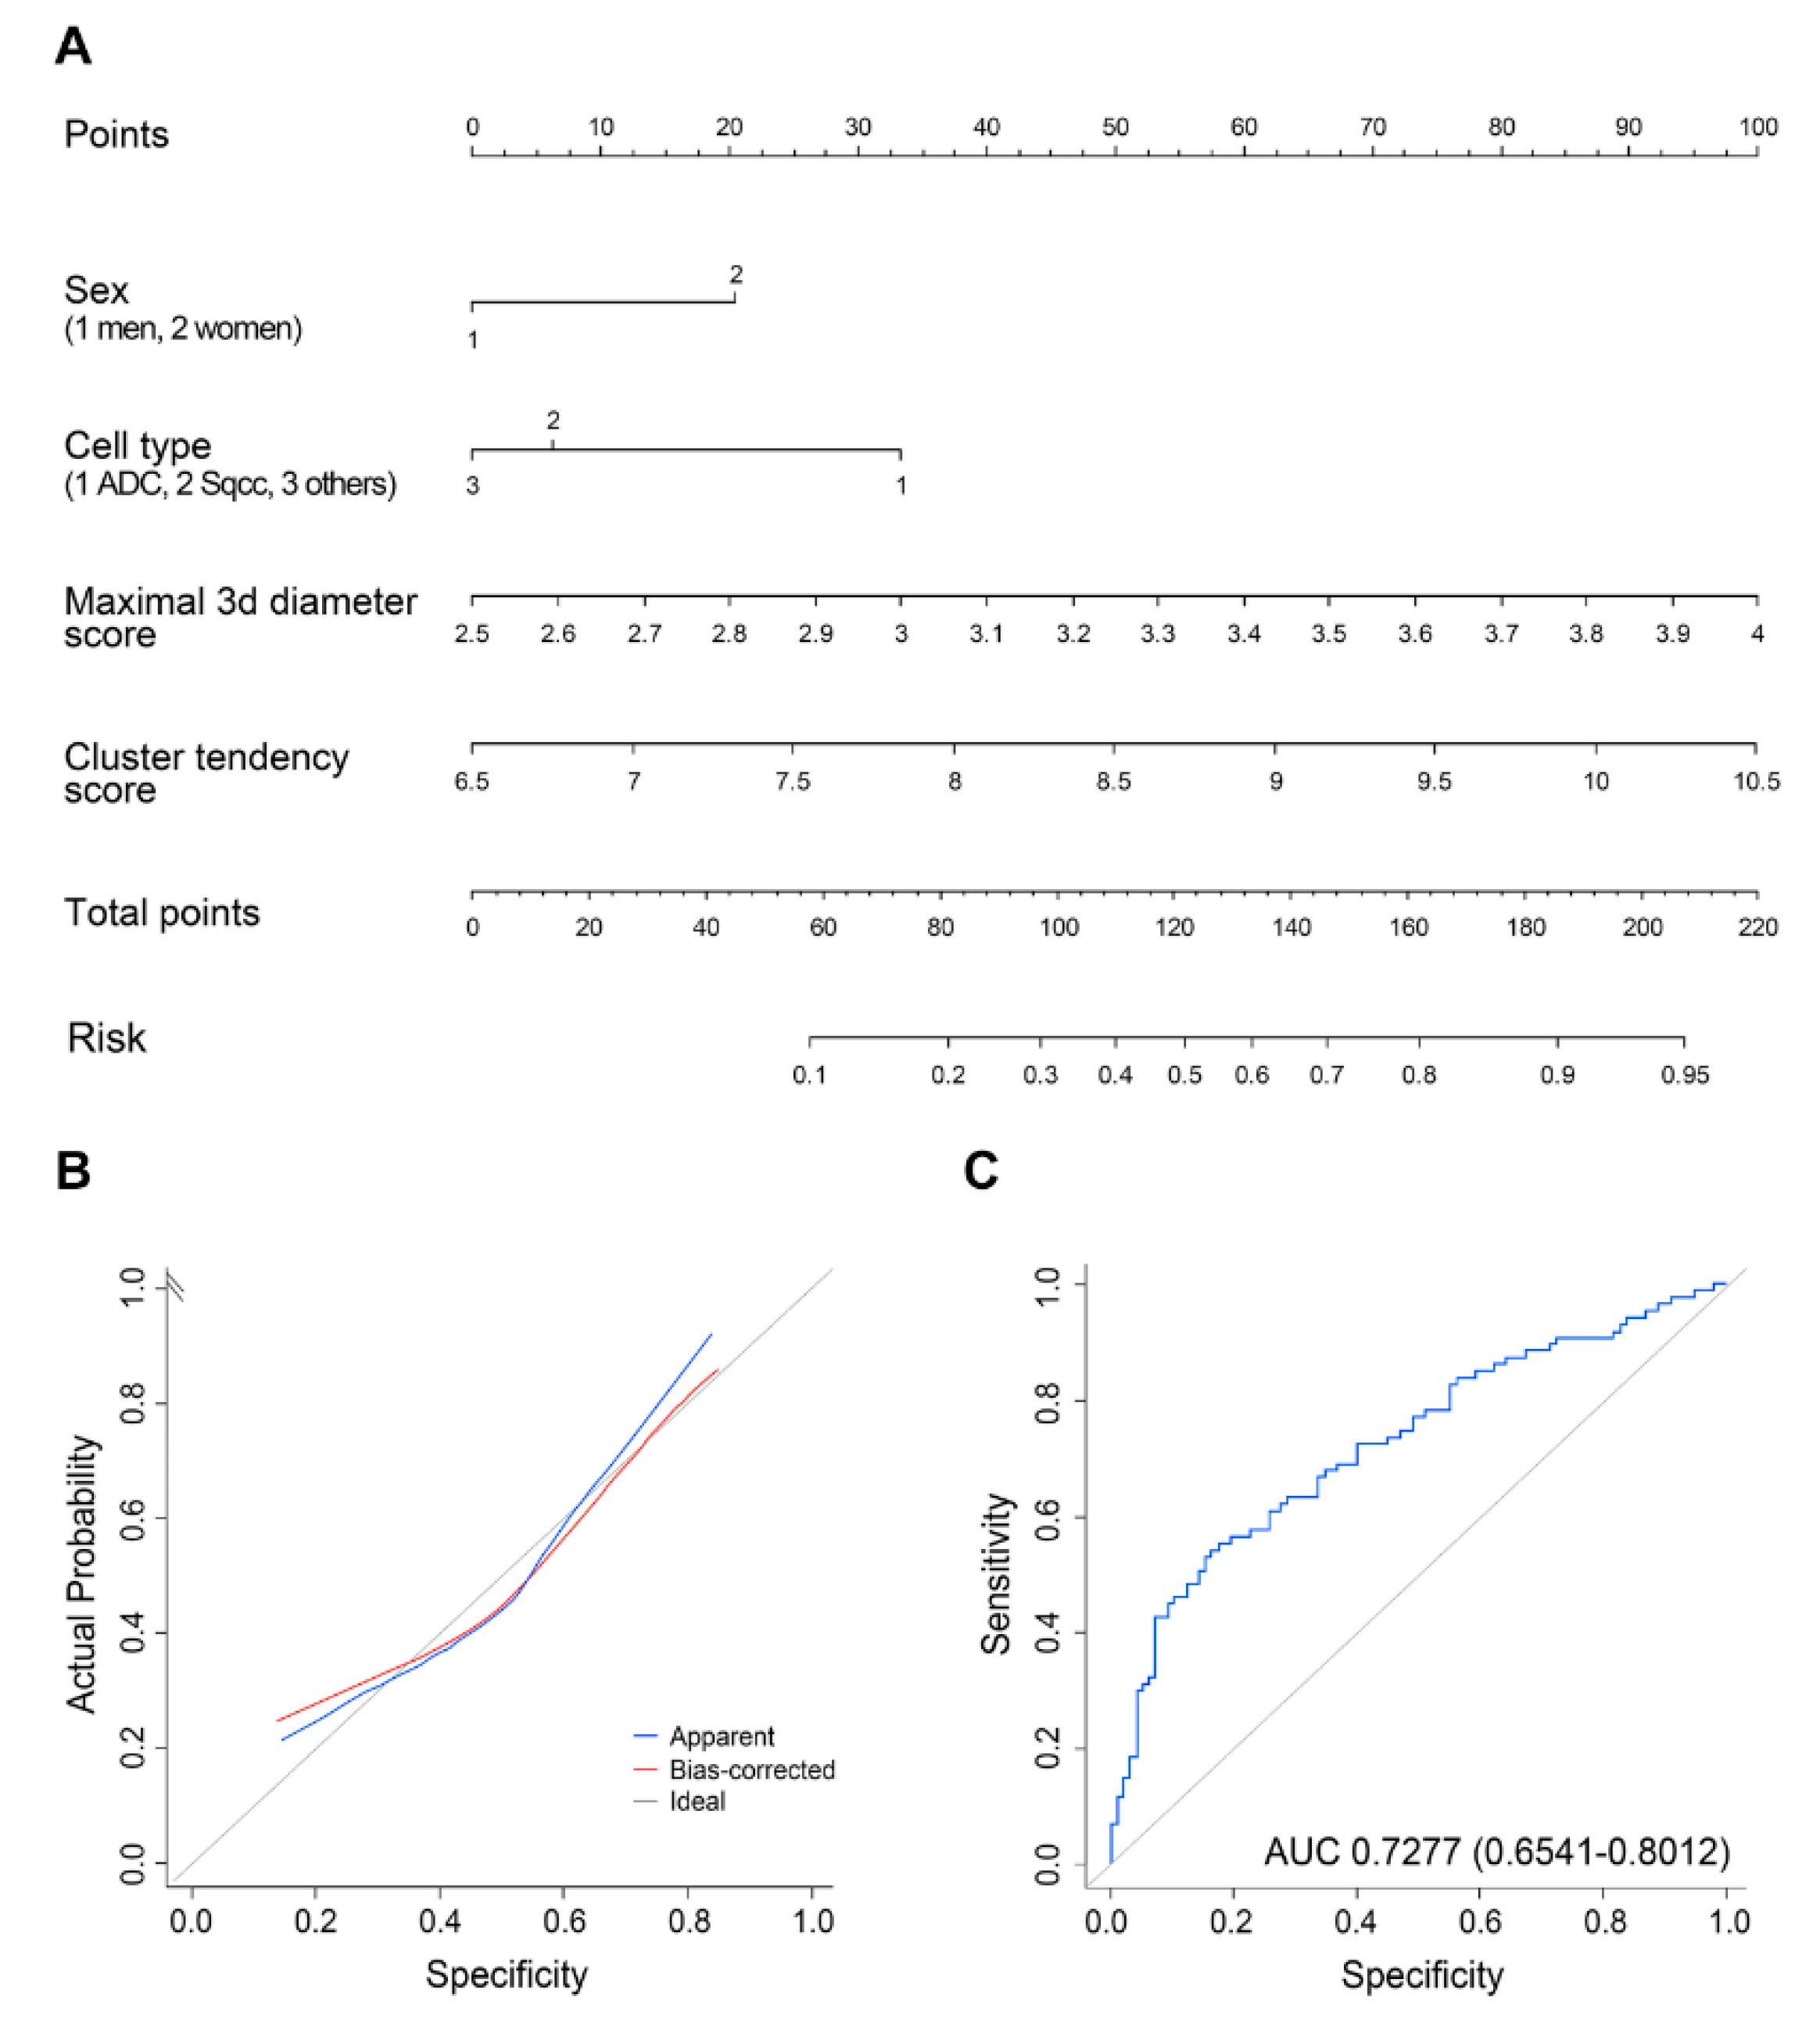

2.2. Analyses of Clinical/Radiomics Variables for Predicting Malignant LNs

| Variable | Reference | OR | 95% CI | p-Value |

|---|---|---|---|---|

| Sex | Male | 2.02 | 0.88–4.62 | 0.096 |

| Cell type | Adenocarcinoma | 0.39 | 0.19–0.77 | 0.0073 |

| Maximal 3D diameter | 9.80 | 3.14–30.61 | <0.0001 | |

| Cluster tendency | 2.36 | 1.23–4.57 | 0.0099 |